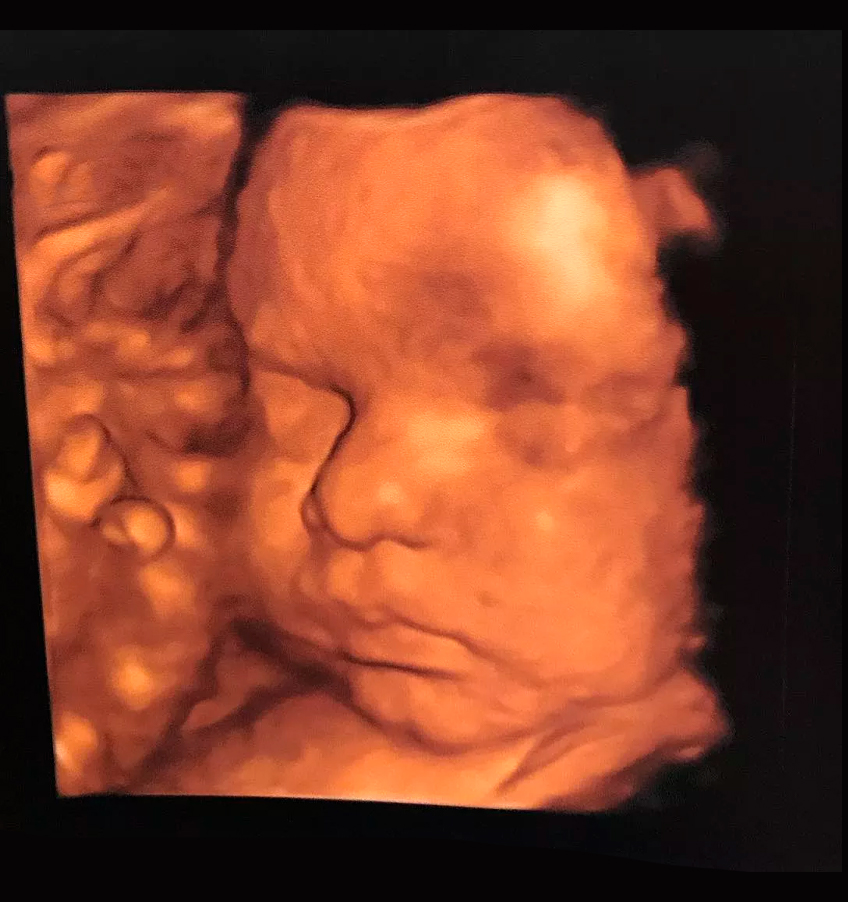

Ultrassons 3D ou 4D

Os ultrassons 3D ou 4D podem ser feitos durante o pré-natal de preferência entre as semanas 26 e 30 e são utilizados para ver detalhes físicos do bebê. O exame em 3D mostra detalhes do corpo do bebê, sendo possível ver o rosto e os órgãos genitais com mais nitidez, enquanto no exame em 4D, além das feições, também é possível visualizar os movimentos do feto na barriga da mãe em tempo real.